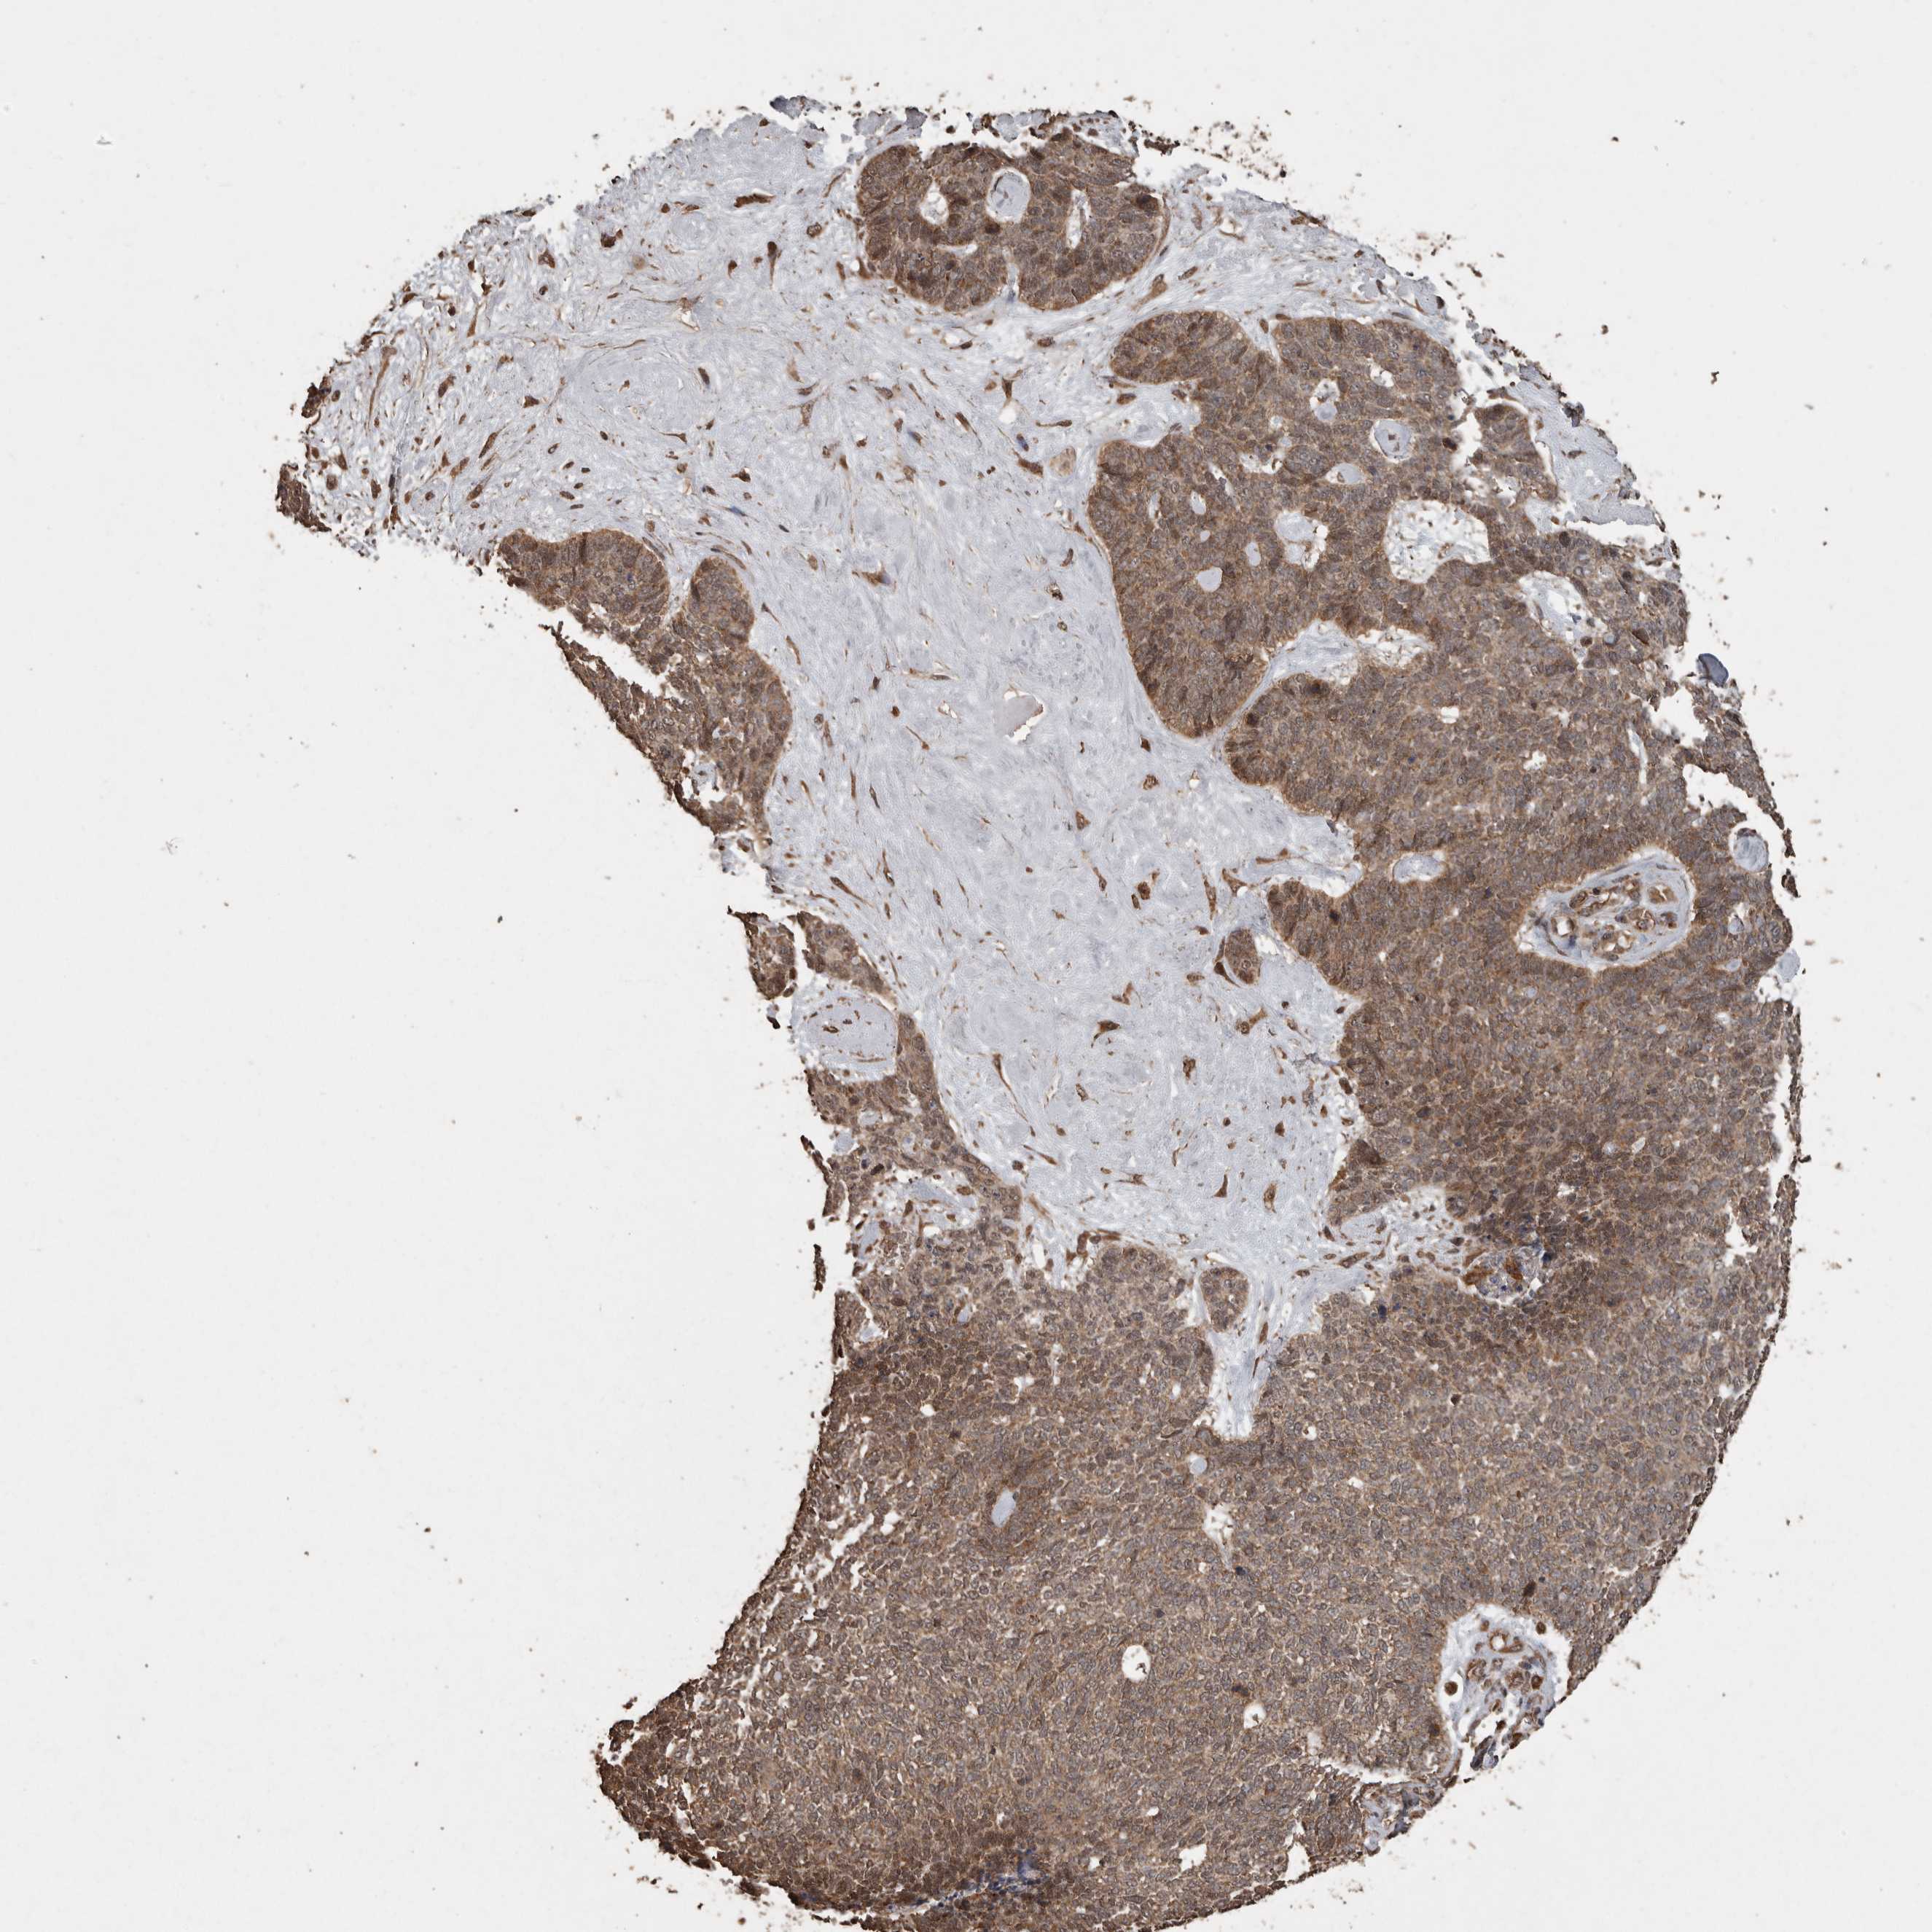

SKIN CANCER - Protein expressioni

A mouse-over function shows sample information and annotation data. Click on an image to view it in a full screen mode. Samples can be filtered based on level of antibody staining by selecting one or several of the following categories: high, medium, low and not detected. The assay and annotation is described here.

Each image is clickable and will lead to virtual microscopy that enables deeper exploration of all samples and also displays staining intensity scores, fraction scores and subcellular localization as well as patient and tissue information for each sample.

Antibody CAB026191

Basal cell carcinoma